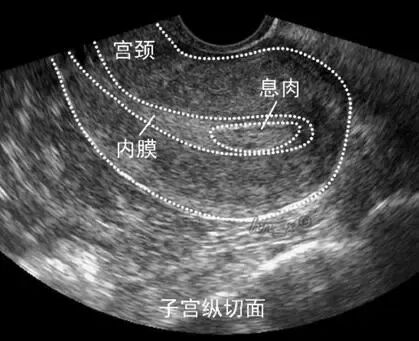

它是子宫内膜局部增生形成的结节状突起,可以单发,也可以多发,小者1~2毫米,大者可充满整个宫腔。

超声是个简便、快捷、无创的检查,在妇产科应用十分普遍。

它可以清楚地显示息肉的大小、位置以及与周围组织的关系,还可以发现盆腔的其他病变。

推荐采用经阴道的三维超声检查,因为二维超声对直径小于1.5cm的息肉可能漏诊,而三维超声检出率则明显提高。

做超声也要选择合适的时机,观察子宫内膜息肉的最佳检查时间是月经干净后3-5天。

此时子宫内膜薄,能更好区分是子宫内膜息肉还是子宫内膜增生,重复做超声也有助于辨别,但最终确诊还是需要组织病理学检查。